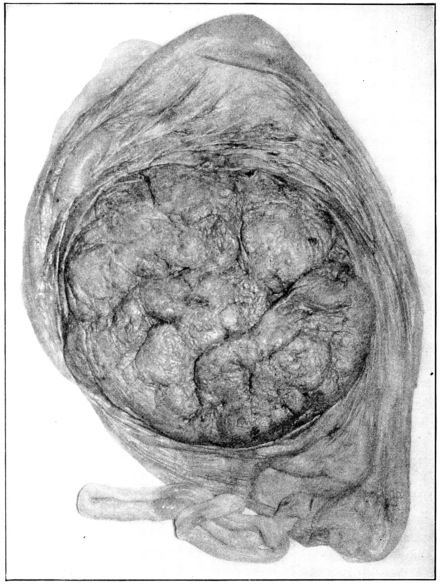

The ovary consists of two parts, the central part or medulla, composed of connective tissue, nerves, blood and lymph vessels, and the cortex, in which are embedded the vesicular Graafian follicles containing the ova. At birth each ovary contains upwards of 50,000 of these ova, which are the germ cells concerned with reproduction and the process of menstruation.

These ovarian glands perform two vital functions, for in addition to their prime function of producing and maturing the germinal cell of the female, they provide an internal secretion 35which exercises an immeasurably important, though imperfectly understood, influence upon the general well-being of the entire organism.